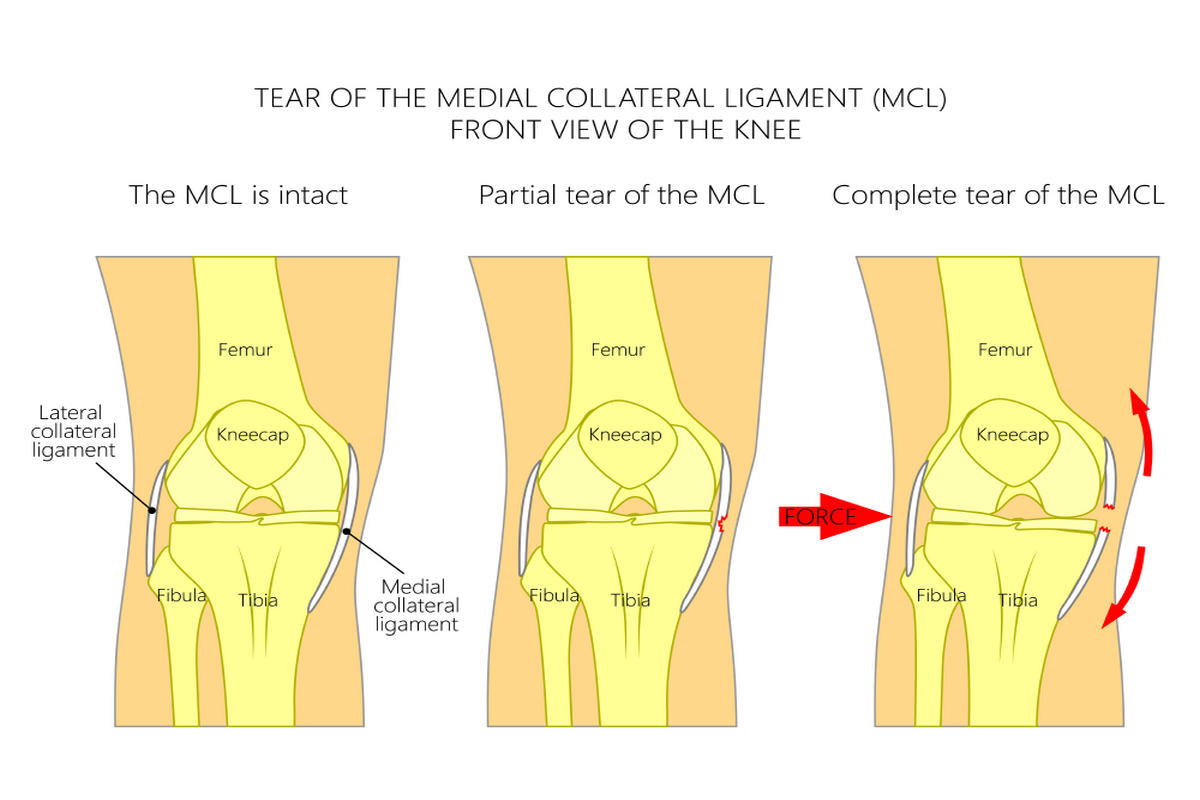

Ο έσω πλάγιος σύνδεσμος (MCL) βρίσκεται στην εσωτερική πλευρά του γόνατος και εμποδίζει την απόκλιση της άρθρωσης προς τα μέσα. Ο έξω πλάγιος σύνδεσμος (LCL) εντοπίζεται στην εξωτερική πλευρά και προστατεύει από δυνάμεις που ωθούν το γόνατο προς τα έξω.

Ο τραυματισμός του έσω πλαγίου συνδέσμου είναι συχνότερος, ενώ η ρήξη του έξω πλαγίου συνδέσμου συνήθως σχετίζεται με σοβαρότερες κακώσεις και συχνά συνοδεύεται από βλάβες άλλων συνδέσμων, όπως ο πρόσθιος χιαστός σύνδεσμος.

Η ρήξη διακρίνεται σε τρεις βαθμούς:

Ρήξη 1ου βαθμού

Ήπια διάταση ή μικρή ρήξη ινών χωρίς ουσιαστική αστάθεια.

Ρήξη 2ου βαθμού

Μερική ρήξη με εμφανές οίδημα, πόνο και μέτρια αστάθεια.

Ρήξη 3ου βαθμού

Πλήρης ρήξη με σημαντική αστάθεια και δυσκολία στήριξης.